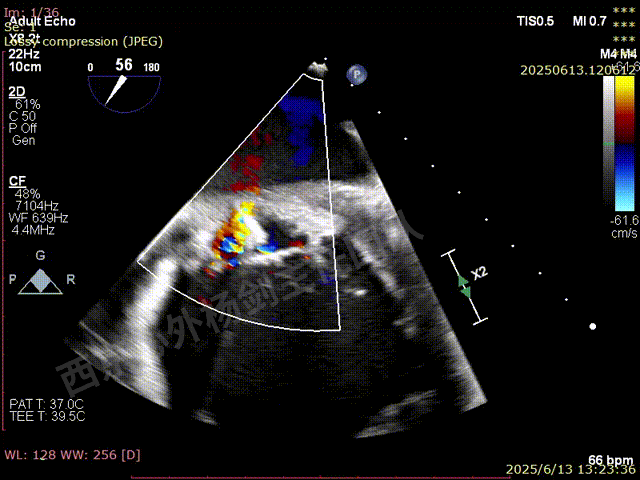

TEER术前超声评估

二尖瓣后叶栓系严重,前叶相对错位,反流束沿2区分布广泛,2偏3区处存在反流。

反流宽度至少23mm,因影像调整困难,考虑实际反流更宽。